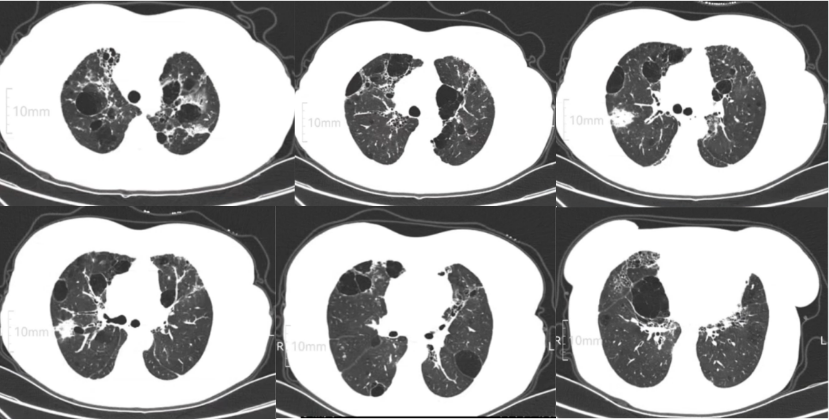

• 胸部CT(图1)考虑间质性肺炎肺气肿,肺大泡冠状血管钙化,主动脉壁钙化

图片

1  患者胸部CT